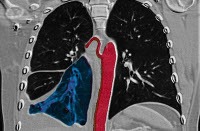

Q33.1 Добавочная доля легкого